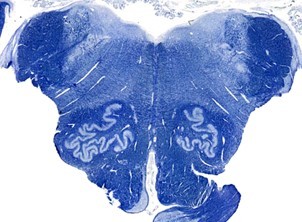

Mid Pons

SLICE 4: Mid pons—main features- root entry zone of CN V, principal sensory and motor nuclei of V. MLF, middle cerebellar peduncle, spinothalamic tract, medial lemniscus, pontine grey matter, corticospinal fibers (disaggregated)